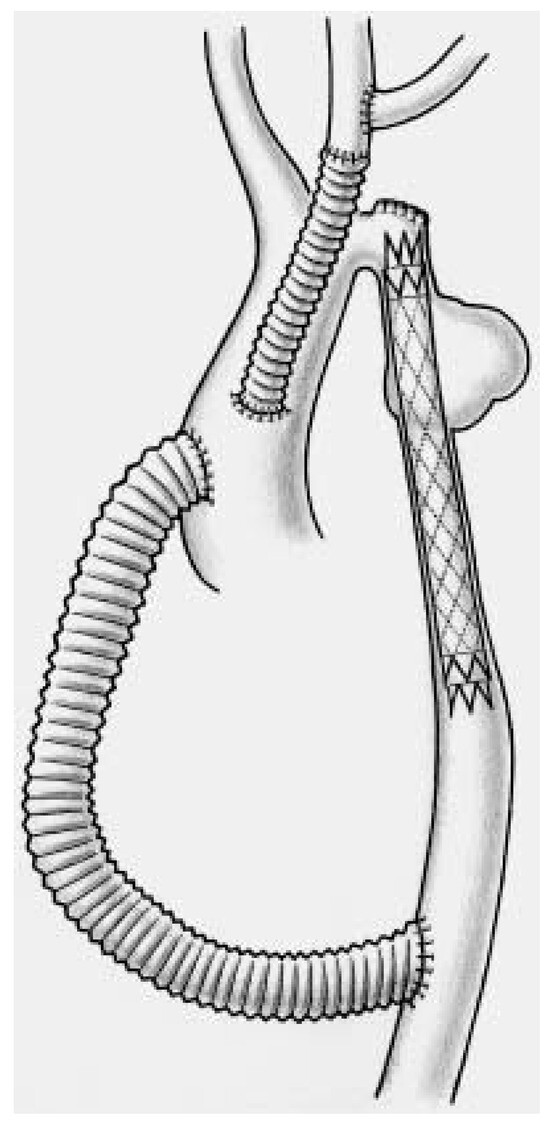

The left subclavian artery is either transposed into the left carotid artery or revascularised at the end of the procedure using an additional 8 mm graft (Figure 3 and Figure 4).

Figure 3. Schematic representation of the combined surgical/endovascular approach which allows complete repair of the aortic arch following debranching and revascularization of the supraaortic vessels.

Finally, a covered Wall-Graft stent-graft prosthesis was inserted within the previous Wallstent, expanded into the mid aortic arch and the proximal descending aorta and allowed complete exclusion of the aneurysm (Figure 5).

Figure 5. Artist drawing of the situation following Wallstent insertion to treat complex coarctation. The hypoplastic aortic arch remained untreated (!!).